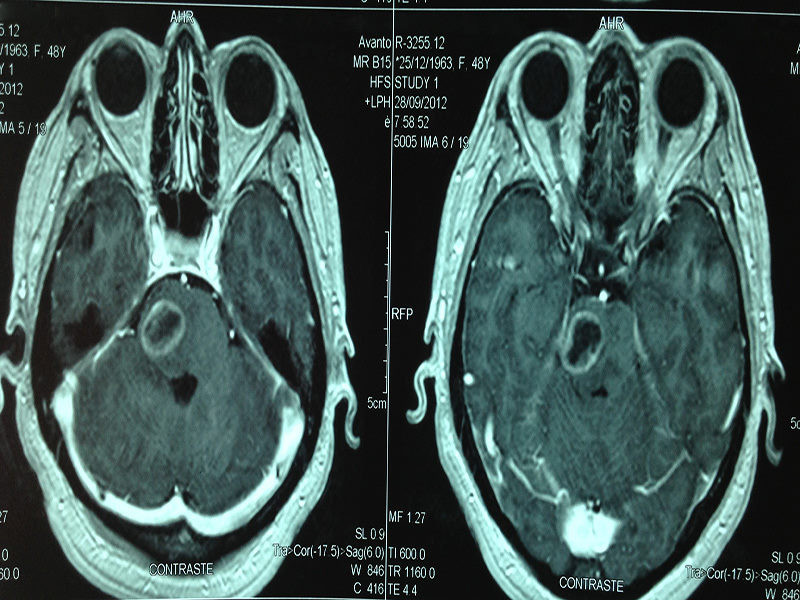

Casos Neuroloquirúrgicos

Envíado por Dr. Ruben Eduardo Amaya Contreras